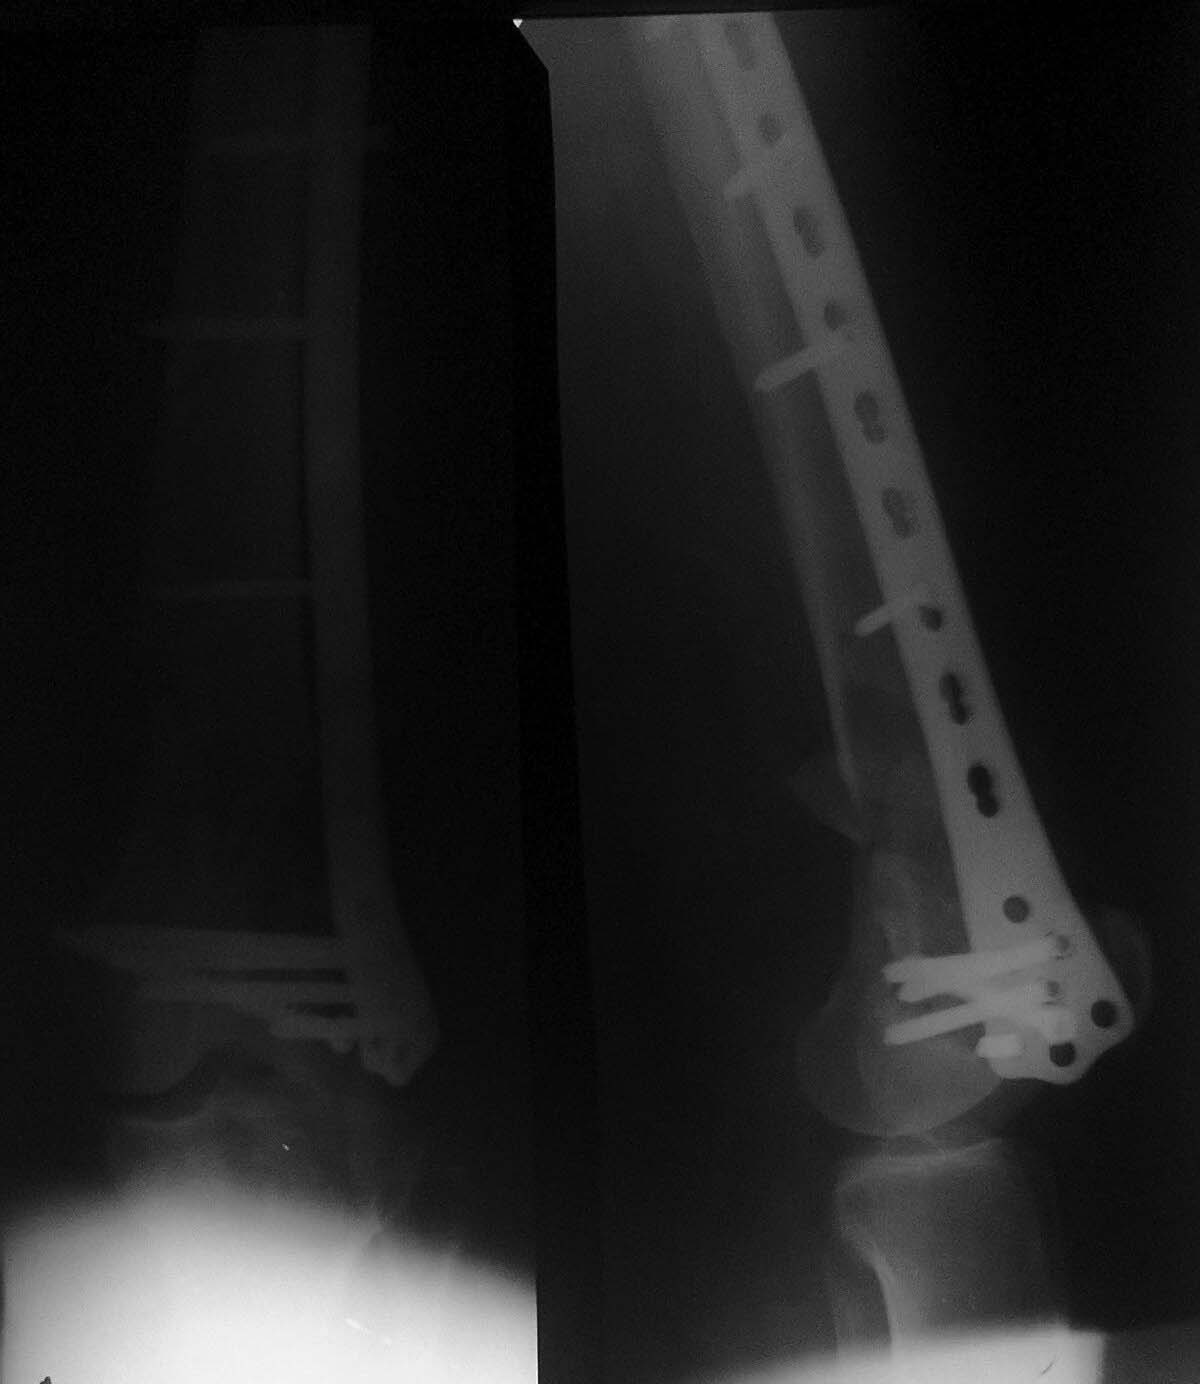

Представляю пациентку Д., 57 лет.Пострадала в ДТП в августе 2014 г.Диагноз:Открытый оскольчатый внутрисуставной перелом дистального метаэпифиза левой бедренной кости со смещением отломков. Рваные раны и ссадины левых бедра и голени. Закрытый перелом V ребра слева без смещения отломков. Травматический шок I ст(снимок 1).

Операция 16.09.14.-Открытая репозиция мыщелков бедренной кости, остеосинтез винтом, закрытая аппаратная репозиция, малоинвазивный остеосинтез бедренной кости опорной мыщелковой пластиной на винтах с угловой стабильностью с контролем под С-дугой(снимок 2).

Сегодня пришла на консультацию (снимок 3). С ее слов: в своей поликлинике ей запрещают до сих пор нагрузку, аргументируя несращением.

Самостоятельно была на консультации в институте травматологии и ортопедии в областном центре, где ей предложили выполнить реостеосинтез с костной пластикой. Стоит ли торопиться с оперативным лечением или дать походить с возрастающей нагрузкой- возможно произойдет полная консолидация? Спасибо всем откликнувшимся!

Формируется несращение. Что приведет к перелому либо винтов, либо пластины. Примерно в эти сроки как раз и происходит разрушение.

Удалять разрушенный имплантат более травматично и трудоемко, чем целый.Так что мы сейчас предочитаем в такой ситуации малоинвазивное удаление пластины и закрытый интрамедуллярный остеосинтез. Здесь бы сделали антеградный. Без костной пластики.

ИМХО, существует высокий риск аваскулярного некроза мыщелков бедра при реостеосинтезе, причем уже по данным последней рентгенографии есть остеолиз зоны перелома латерального мыщелка.

Рассмотрим ошибки остеосинтеза. А тогда станет понятно что делать.

1. Нет межфрагметарной компрессии и анатомической репозиции внутрисуставного перелома. Это временем не устранить.

2.На пластине максимально "укоротили" рабочую зону кортикальным винтом. Нет адекватного шинирования - нет сращения. Временем тоже не устраняется.

3.Певичная костная пластика. Тоже вопрос.